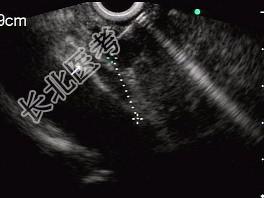

- 单项选择题男性,50岁, 上腹隐痛,食欲不振3个月。1个月来出现黄疸且进行性加深, 体重明显减轻,查体全身明显黄染, 肝未触及,深吸气时可触到肿大胆囊底部, 无触痛。化验血胆红素15mg/dl,尿检胆红素阳性图中胰腺病变可能的诊断是 ( )

E、胰腺癌